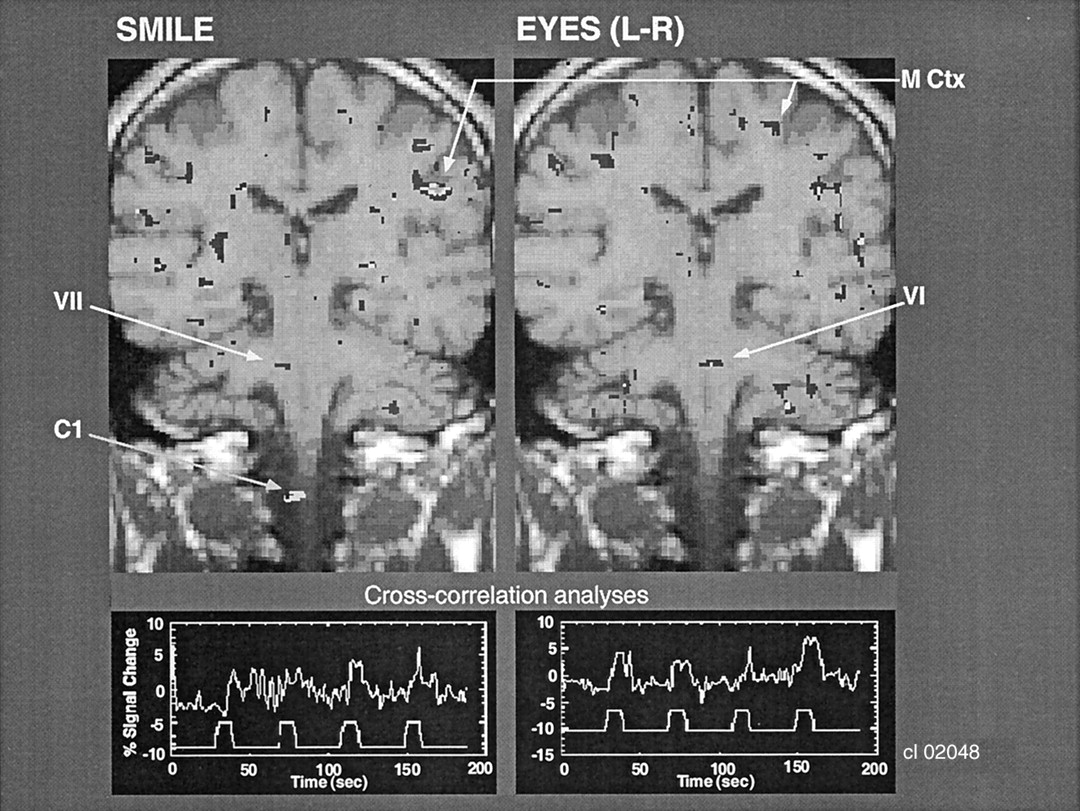

Figure 2 shows a comparison of the regions of BOLD activity in the same individual in the same brain section obtained with two tasks that involve closely adjacent, but different, CN motor nuclei. The task of alternating between smiling and puckering the lips was correlated with BOLD activation in the region of the facial nucleus (CN VII). By contrast, eye movement (ie, shifting the eyes laterally with alternating left-to-right movement) was correlated with BOLD activation in the pons in the region of the abducens nucleus (CN VI), which provides the motor innervation of the lateral rectus muscles of the eye. The abducens nucleus is near the midline, whereas the facial nucleus is lateral to it, at about the same level of the neuraxis. Note that the region of BOLD activation in the cortex corresponded to the homuncular region of the face, consistent with the activation in the brainstem. Also shown in Figure 2 is the cross-correlation time series data. The upper part of each of the traces shows the time course of the BOLD signal change in these ROIs. The lower part shows the time course of the stimulus input; the peak represents the activity of the paradigm, which alternates with the baseline.

Coronal images show that facial and eye movements activate different adjacent brain regions that correspond to the facial and abducens CN nuclei, respectively. Cross-correlation analysis was performed between the onset and termination of the movements and the BOLD signal change in these pontine regions of activation. C1 indicates the C1 level of the spinal cord; M Ctx, motor cortex; VI, CN VI, and VII, CN VII.

Figure 5 shows interindividual reliability in the region of BOLD activation in correlation with left-to-right eye movement. The pontine location of activation near the midline was consistent with activation of the abducens nucleus (CN VI). Figure 6 shows that the region of BOLD activation in relation to finger tapping was consistent among three individuals. This finding corresponded to the region of the nucleus cuneatus, which receives afferent activity from the hands. In addition, the region of BOLD activation in the sensory cortex corresponded to the homuncular region for the fingers (note that this region of activation was superior to that in the face in Figure 2). Furthermore, in one subject (right image), BOLD activation was evident in the somatosensory thalamus (region of the nucleus VPL); this finding was consistent with afferent activation from the fingers.